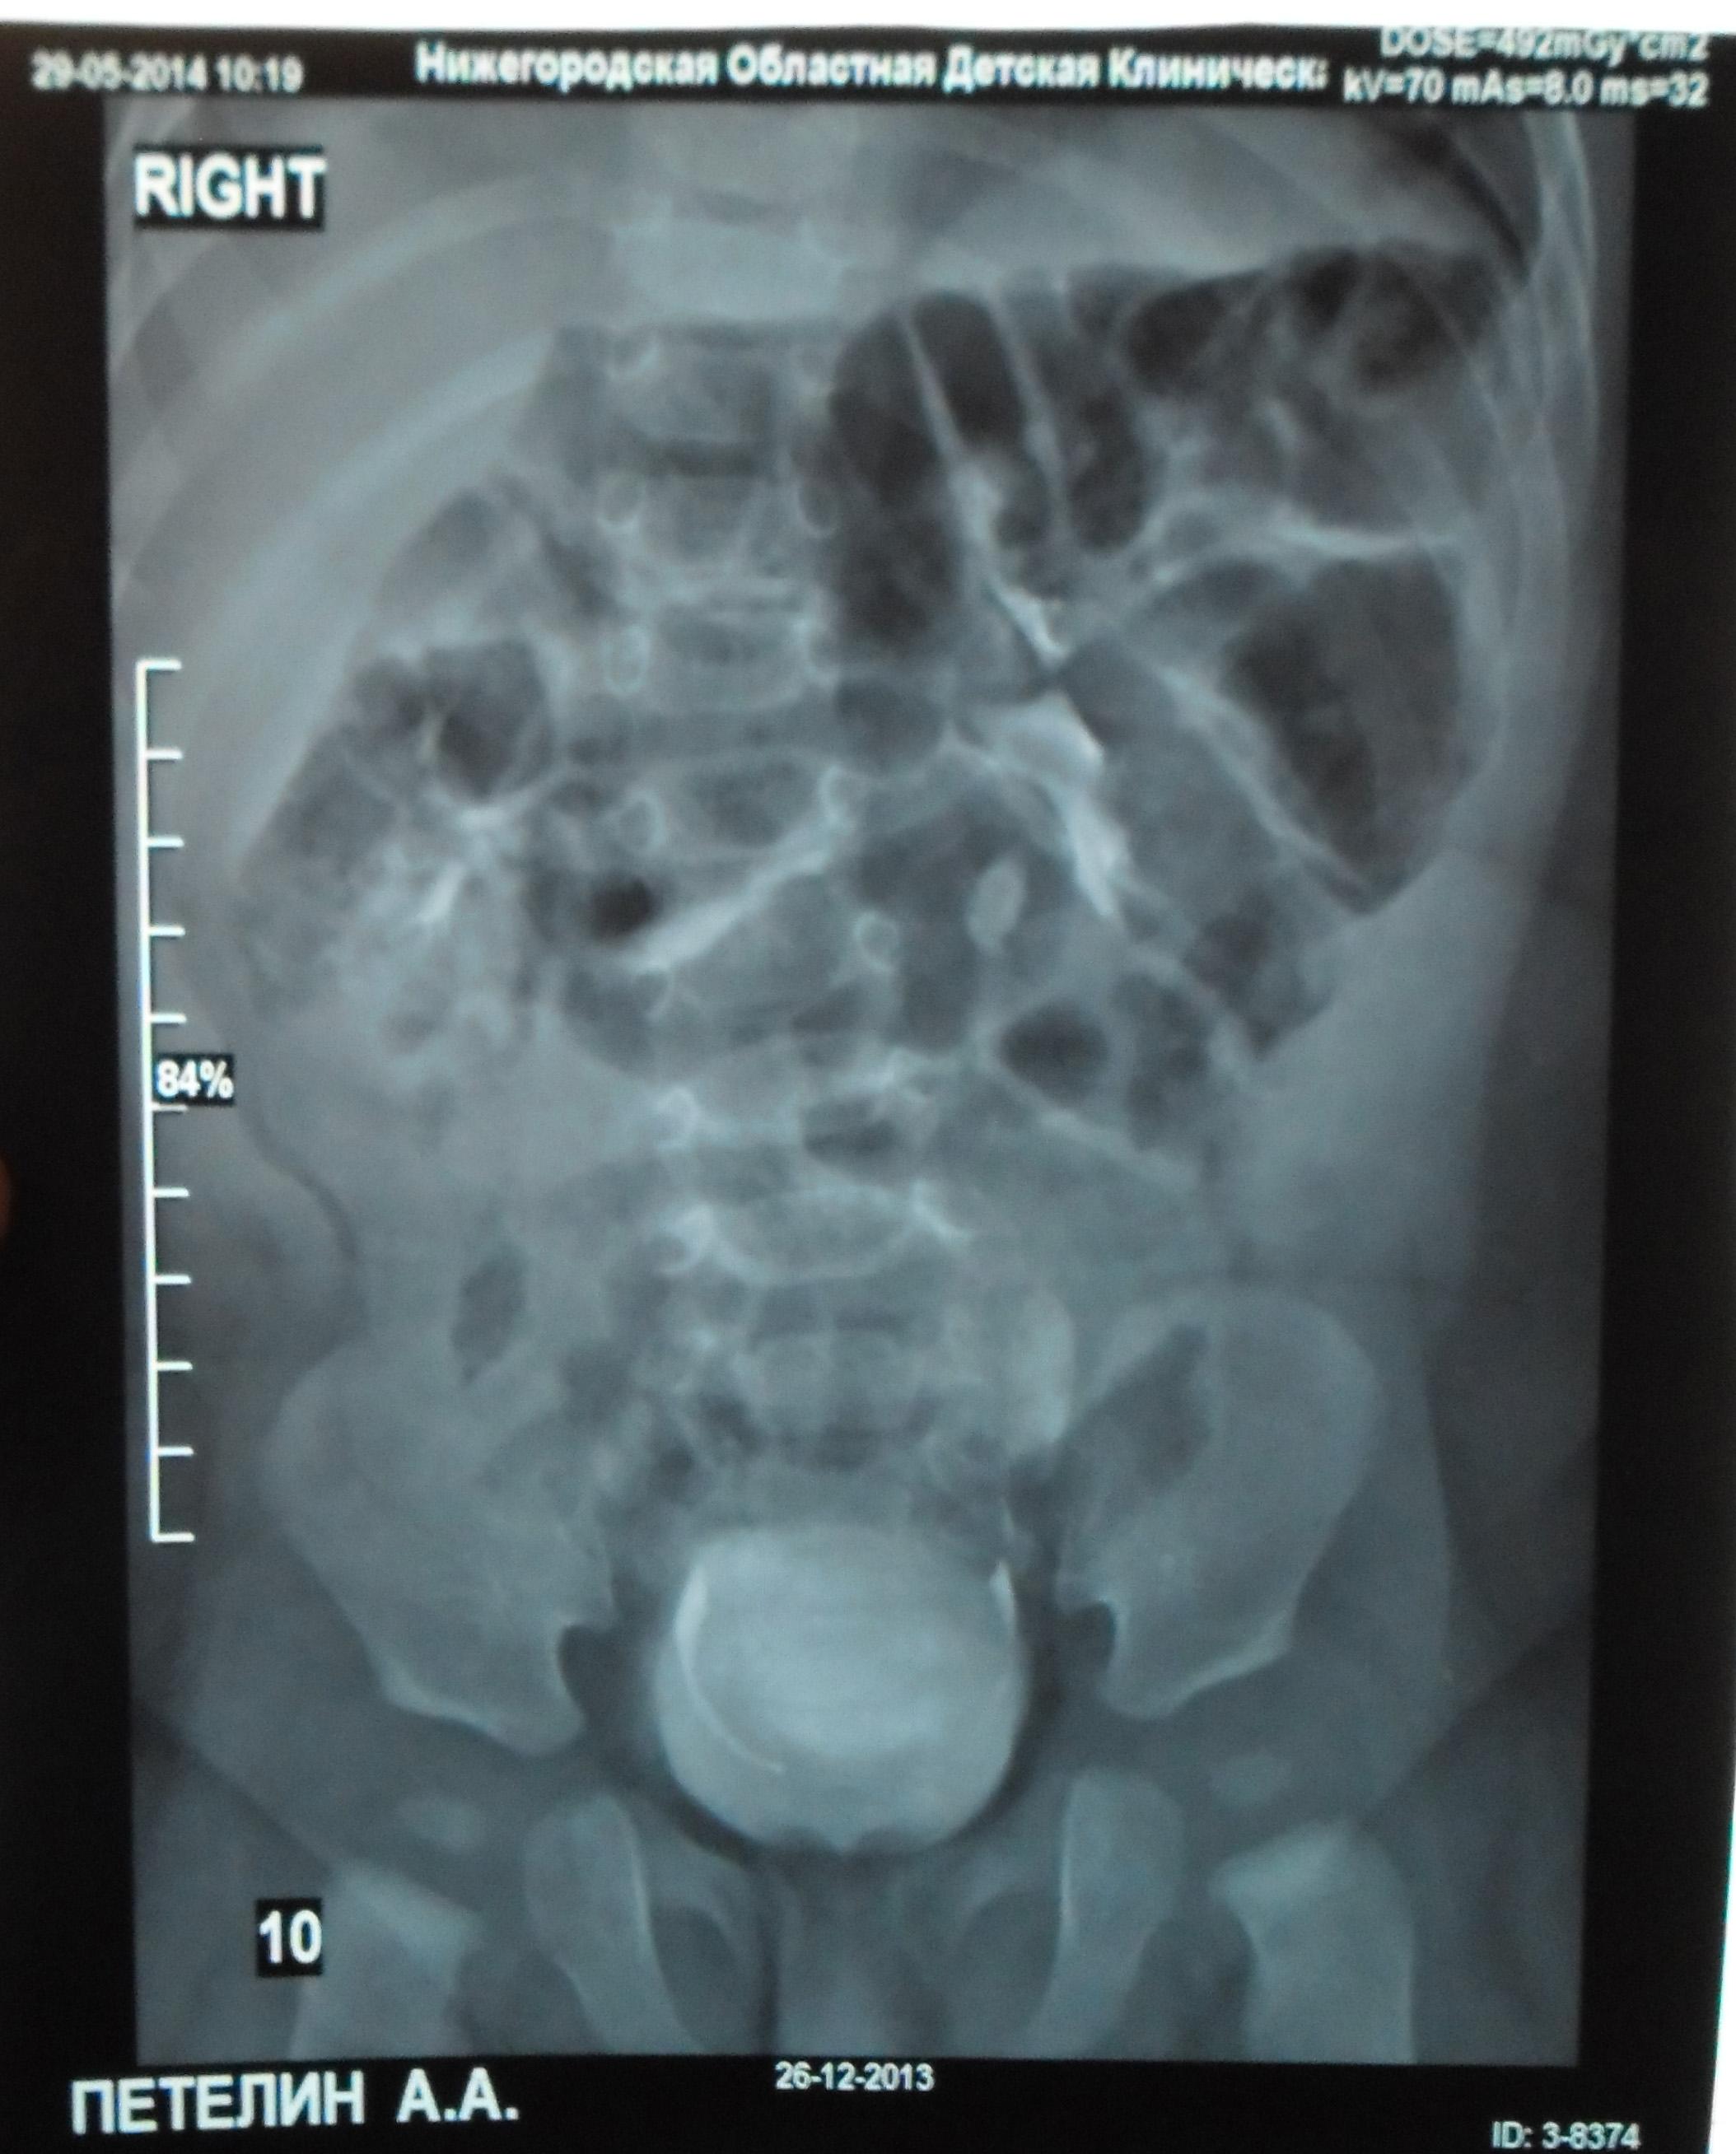

Моему ребенку 1 год 1 месяц. Во время беременности у плода было обнаружено увеличение лоханки слева - 9мм. Далее по результатам УЗИ после рождения максимальное увеличение достигало 17 мм. В 5 месяцев проходили урологическое обследование, результаты цистографии: мочевой пузырь округлой формы. Контуры ровные. ПМР нет. ЭЭД-1,2МЗВ; урографии: рентгеноконтрастных теней конкремента нет, почки в типичном месте, размеры сохранены, структура ЧЛК справа не изменена, слева пиелоэктазия, подвижность допустима, функция сохранена, ЭЭД – 0,4 МЗВ. По последнему УЗИ (1 год) увеличение лоханки слева - 28 мм. Мочеточники и сама почка в норме. Результаты анализов мочи за этот год хорошие (сдавали ежемесячно). В чем могут быть причины данного явления и чем это грозит малышу?

Ответ врача

В данном случае - сужение лоханочно-мочеточникового сегмента и\или добавочный сосуд(слева). Но выделительная функция почки сохранена. В данный момент целесообразно наблюдение, но в дальнейшем - не исключено хирургическое вмешательство.